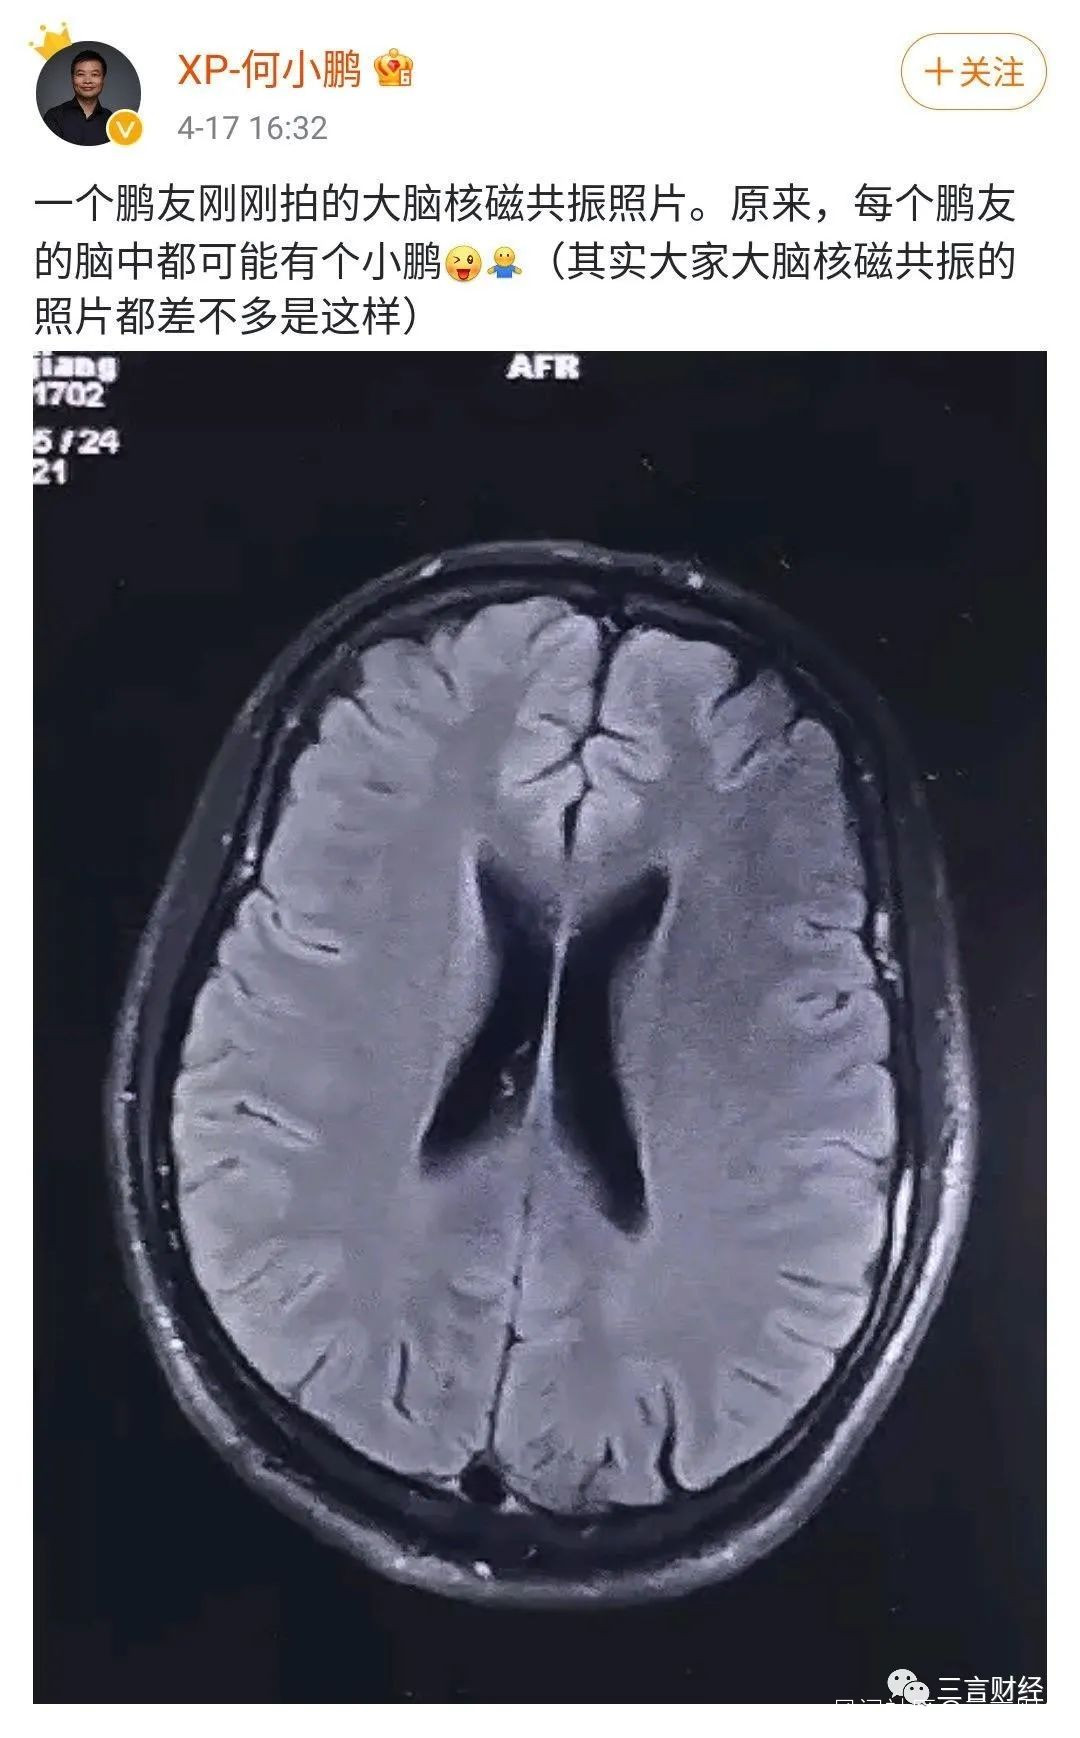

去年4月份,何小鵬用車主的腦部核磁圖做宣傳,也是腦洞大開,當時引發廣泛爭議,後來何小鵬也主動刪了該條微博。